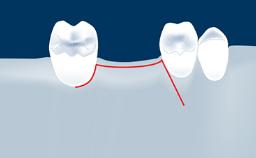

- intraoperative complications of lateral window sinus floor elevation

- intraoperative complications of transcrestal sinus floor elevation

- postoperative complications of sinus floor elevation